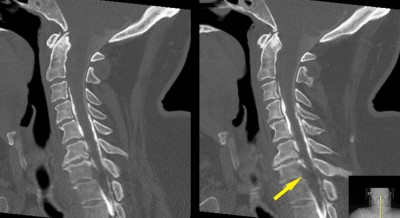

C-spine MRI. Midsagittal image (left) shows C7-T1 malalignment and disc displacement (yellow arrow). Axial images (left) are degraded by patient motion during the MRI scan. They show probable disc displacement and cord compression at C7-T1, but are inadequate to plan surgery. Disc displacement is shown by yellow arrow and spinal cord is designated by yellow star.